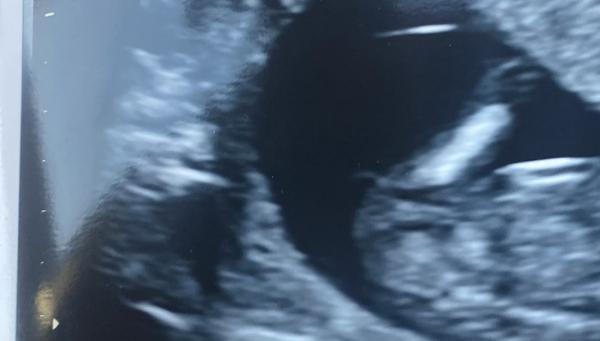

Holky ještě jsem našla tuhle fotku k porovnání, není to teda úplně 100% ale podle toho bych asi tipla taky spíše kluka (naše je ta první fotka). I když to zatím není úplně směrem nahoru a hrbolek je více vytyčený dopředu, ale asi spis kluk, co?

@sishina kluk a nebo šňůra😁 ale jestli doktor říkal v pozdějším ultrazvuku kluka, tak to asi bude spíš on..u mě ještě čekali, jestli teprv pinďa nevyleze a holku mi potvrdil na 99% až okolo 18tt🙂

@laxesis utz, kde padl rozsudek byl 12+4 🤭

@sishina 12+4 je ještě čas, sledovala jsem teorii nuba do 13tt může nub stoupnout. Myslím si spíš chlapečka 💙😊